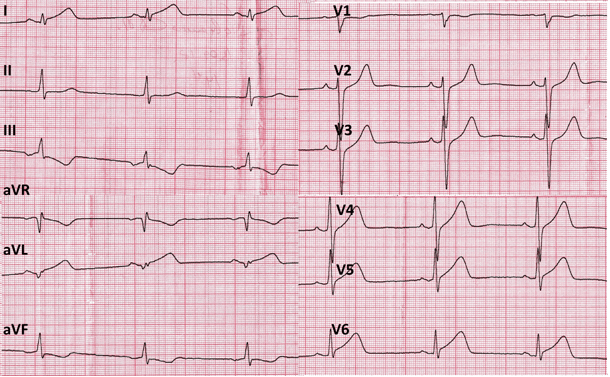

Мужчина, 37 лет. Пациент считал себя здоровым человеком, хронических заболеваний и вредных привычек не имел. От занятий по физической подготовке не освобождался и отмечал хорошие спортивные результаты (высший квалификационный уровень). Важными анамнестическими сведениями явились данные о внезапной смерти отца в возрасте 54 лет. В 2018 году после сдачи нормативов по физической подготовке (бег на 1 км), впервые в жизни возник приступ интенсивной давящей боли за грудиной с иррадиацией в левую руку, сопровождавшийся резкой слабостью, профузный холодным потом, тошнотой с однократной рвотой. После непродолжительного отдыха боль не купировалась, в связи с чем обратился в медицинский пункт. На ЭКГ была выявлена элевация сегмента ST в отведениях I, aVL, V5-V6, а также реципрокные изменения в виде депрессии сегмента ST и инверсии зубца Т в отведениях III и aVF. По этому поводу бригадой скорой медицинской помощи с диагнозом «Острый коронарный синдром c подъёмом сегмента ST» был доставлен в Военно-медицинскую академию им. С.М. Кирова.

При поступлении в Военно-медицинскую академию им. С.М. Кирова при объективном обследовании, за исключением ослабления первого тона на верхушке сердца, других патологических изменений выявлено не было. Результаты клинических анализов крови и мочи были в пределах нормы. В лёгочной ткани очаговых и инфильтративных изменений не наблюдалось, корни лёгких были чёткие и структурные, синусы свободные, тень сердца не расширена. ЭКГ соответствовала переходу острейшей ЭКГ-стадии проникающего инфаркта миокарда в области передней и боковой стенок левого желудочка в острую (рис. 1). По данным биохимического исследования крови: тропонин-Т – 8,06 нг/мл, КФК – 2490 МЕ/л, КФК-МБ – 196,28 МЕ/л. При эхокардиографическом исследовании наблюдалось уплотнение стенок аорты, камеры сердца были нормальных размеров, клапанный аппарат без особенностей. Расчётное давление в лёгочной артерии в пределах нормы. На фоне сохранённой общей сократительной функции левого желудочка (60% по Simpson) были выявлены зоны акинезии в средних и верхушечных сегментах его передней и боковой стенок. На основании полученных данных был установлен диагноз: «Острый проникающий инфаркт миокарда в области передней и боковой стенок левого желудочка» и принято решение о необходимости проведения рентгенэндоваскулярной диагностики и лечения острого инфаркта миокарда (рис. 2, 3 и 4).